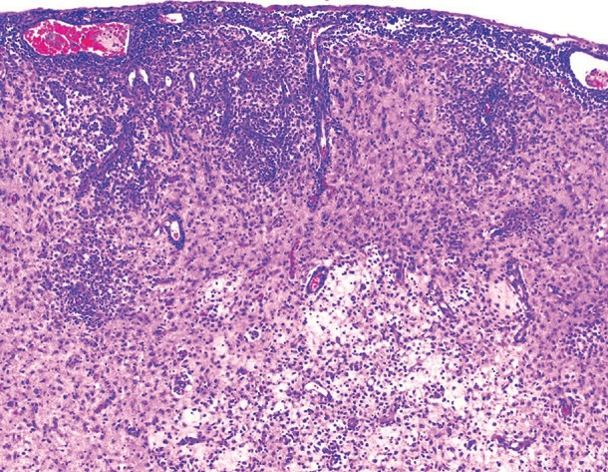

9

What is this?

Angiocentric encephalitis